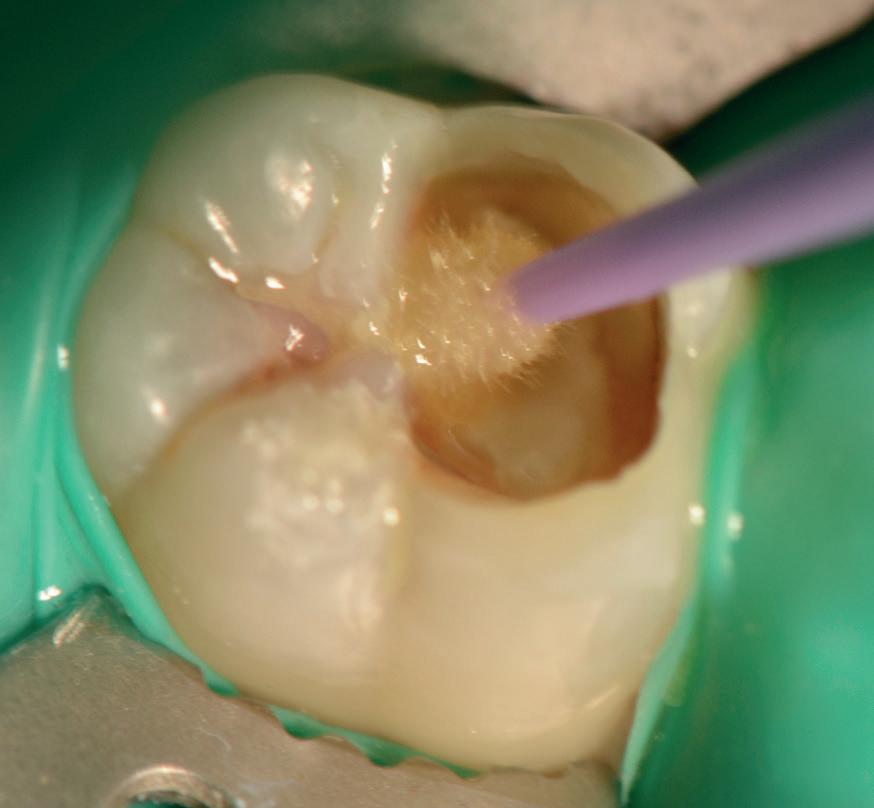

Predictable management of a deep carious lesion, page 27

•

• Continue to monitor and support